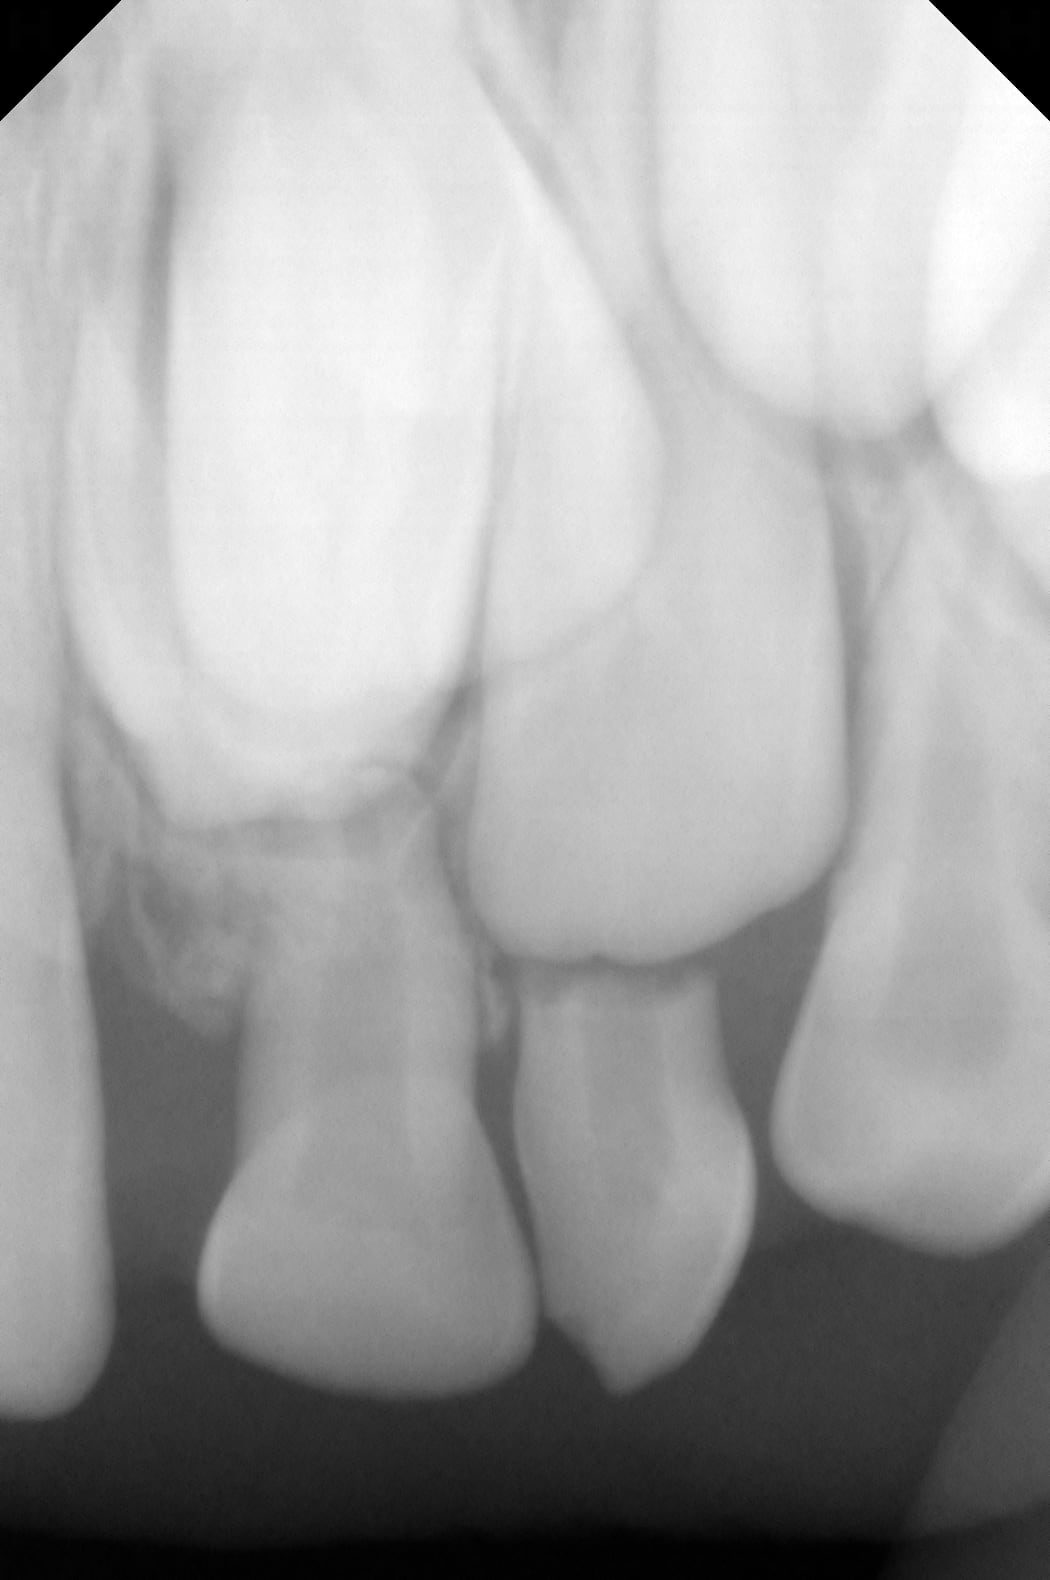

21 et 22 n'ayant pas évolué, je prends un cliché qui me montre ce que je pense être un mesiodens accolé à la 21.

- ensuite, en tant qu'omnipraticienne, en quoi se permet-elle d'émettre un diagnostic ortho aussi délirant (elle n'a ni vu le mesiodens, ni la 22 qui, comme vous pouvez le constater, est bel et bien présente)?